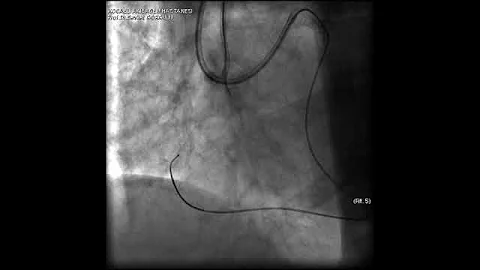

Aortic Dissection And Radial Rupture During Retrograde Cto Pci: Management Of Complications Vİdeo 25